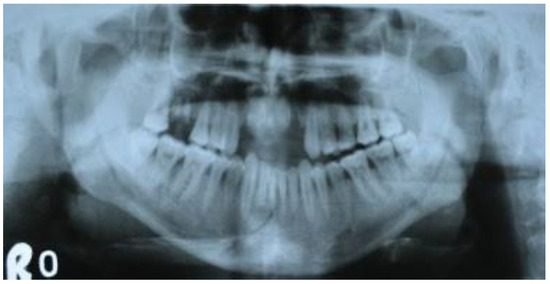

Six out of seven patients showed good anatomical reduction on postoperative CT scans (Figure 6, Figure 7, Figure 8 and Figure 9) and orthopan-tomograph (Figure 10, Figure 11, Figure 12 and Figure 13). On regular follow-up at 3 weeks, 3 months, and 6 months, and 1 year, no evidence of wound dehiscence, discrepancy in occlusion, or lower border malalignment was seen (Figure 14).

Figure 12. Case 2: Preoperative orthopantomograph showing interforaminal mandible fracture of left side.